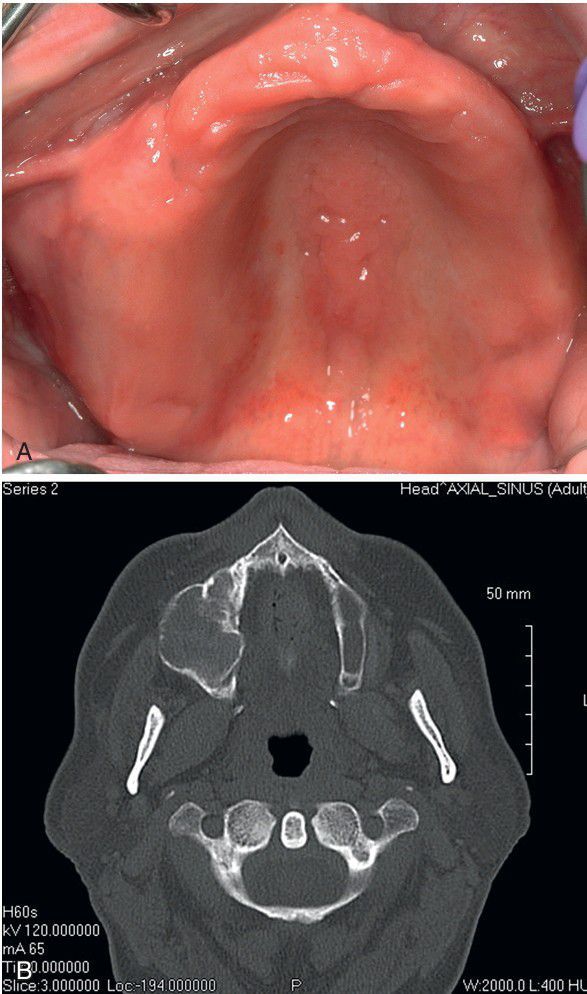

Ossifying Fibroma.

Clinical image (A) and computed tomography (CT) scan (B) showing a large, expansile lesion of the posterior maxilla.